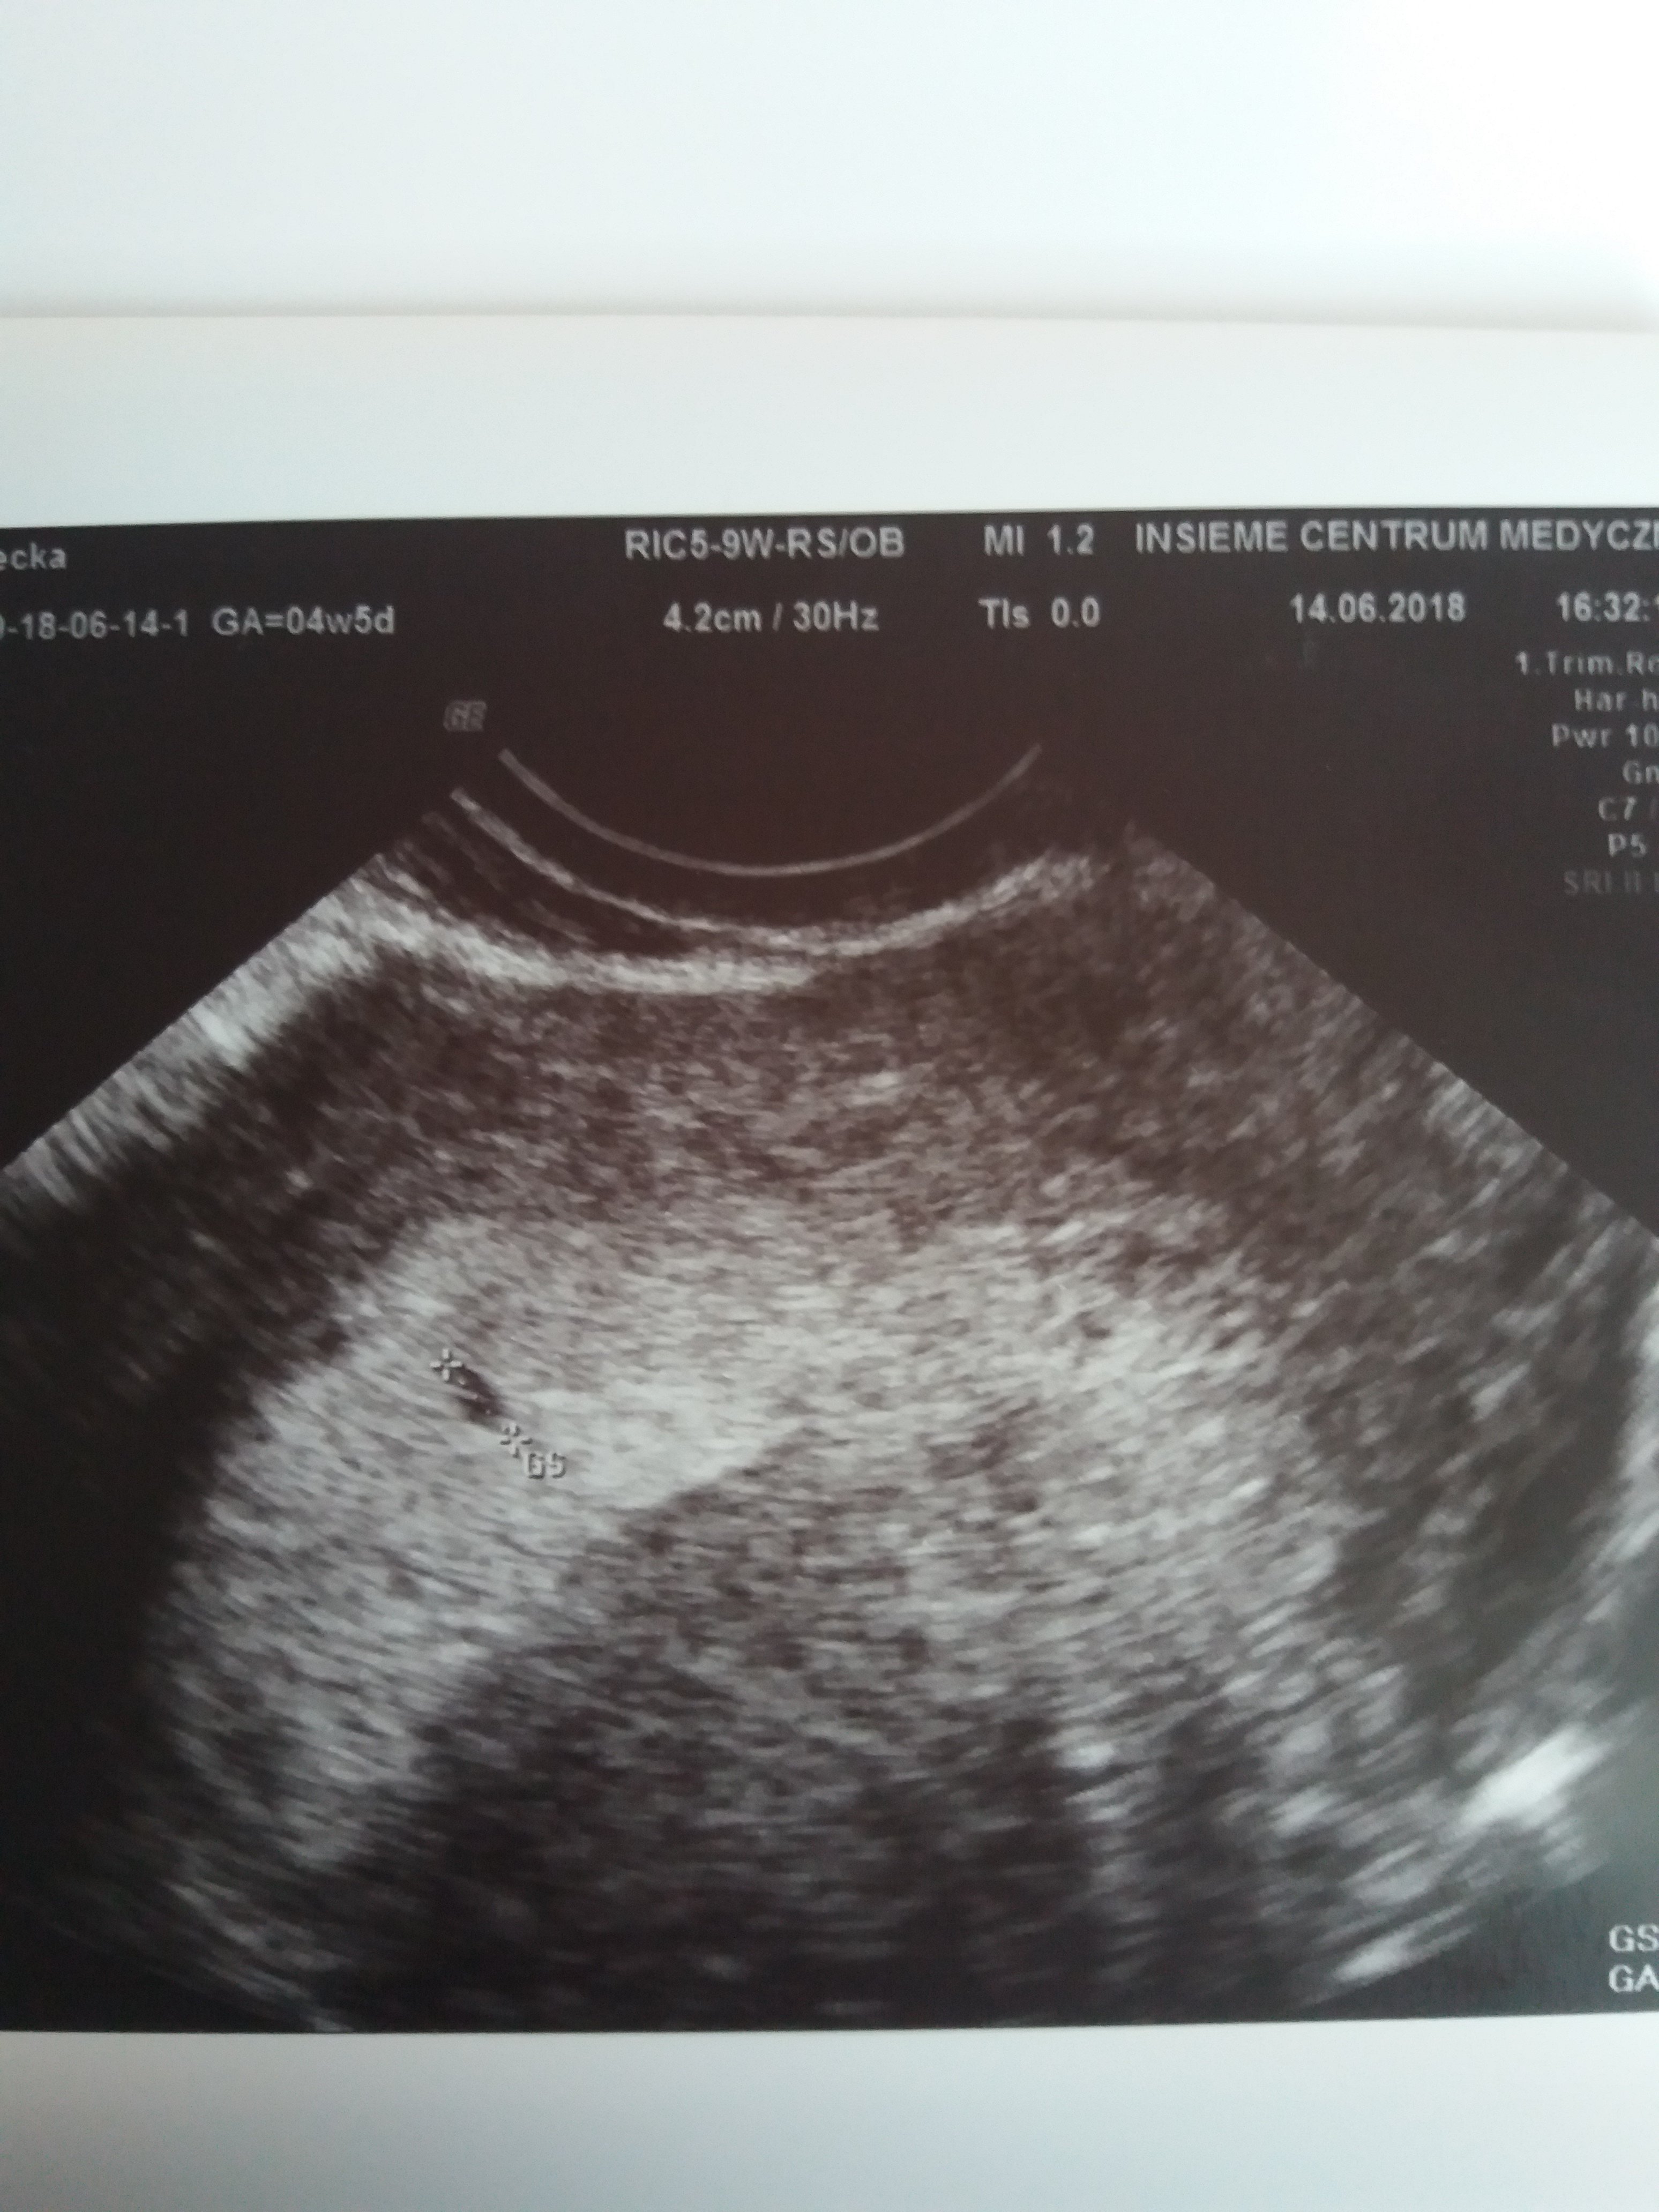

Patrzcie na moją pestke jaka malizna :D

Załączniki

• 20180614_183230.jpg

20180614_183230.jpg

1,1 MB · Wyświetleń: 139